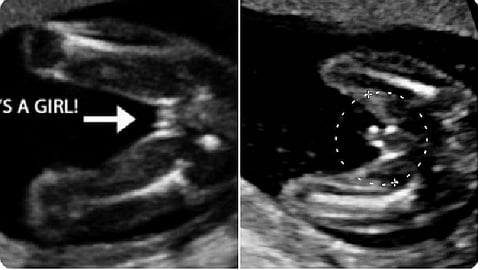

وأشارت في تغريدة عبر حسابها الرسمي على تويتر، إلى أن تحديد جنس الجنين يعتمد على رؤية الأعضاء التناسلية بالأشعة.

3 - وضعية الجنين.